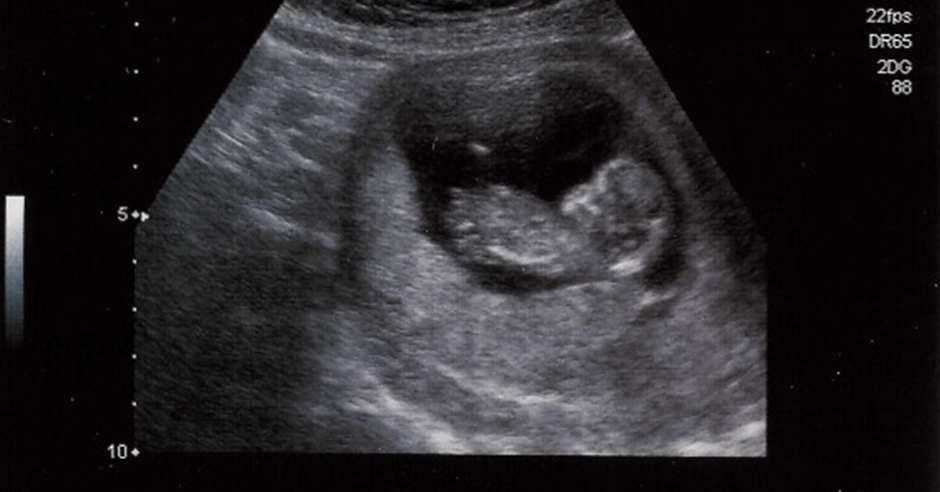

Samen met de TU/e heeft Blank twee methodes ontwikkeld waarmee eenvoudig, betrouwbaar en objectief de samentrekkingen van de niet-zwangere baarmoeder gemeten kan worden. Blank: “Hierbij gaat het om een electrohysterografie (EHG) en Speckle Tracking met 3D echografie. Het klinkt moeilijker dan dat het is. Voor de EHG metingen worden er stickers op de buik bij de vrouw geplakt en meten we samentrekkingen, voor de vrouw totaal niet belastend. Je kunt het vergelijken met een hartfilmpje (ECG). We meten alleen nu niet de elektriciteit die het hart afgeeft, maar die van de baarmoeder. Met Speckle Tracking volgen we puntjes in het echobeeld gedurende een aantal minuten en als deze dan naar elkaar toe bewegen kunnen we dat zien als een samentrekking.